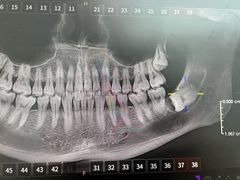

• -牙博士口腔品牌连锁(杨浦店)

panda | 25-11-13

报错